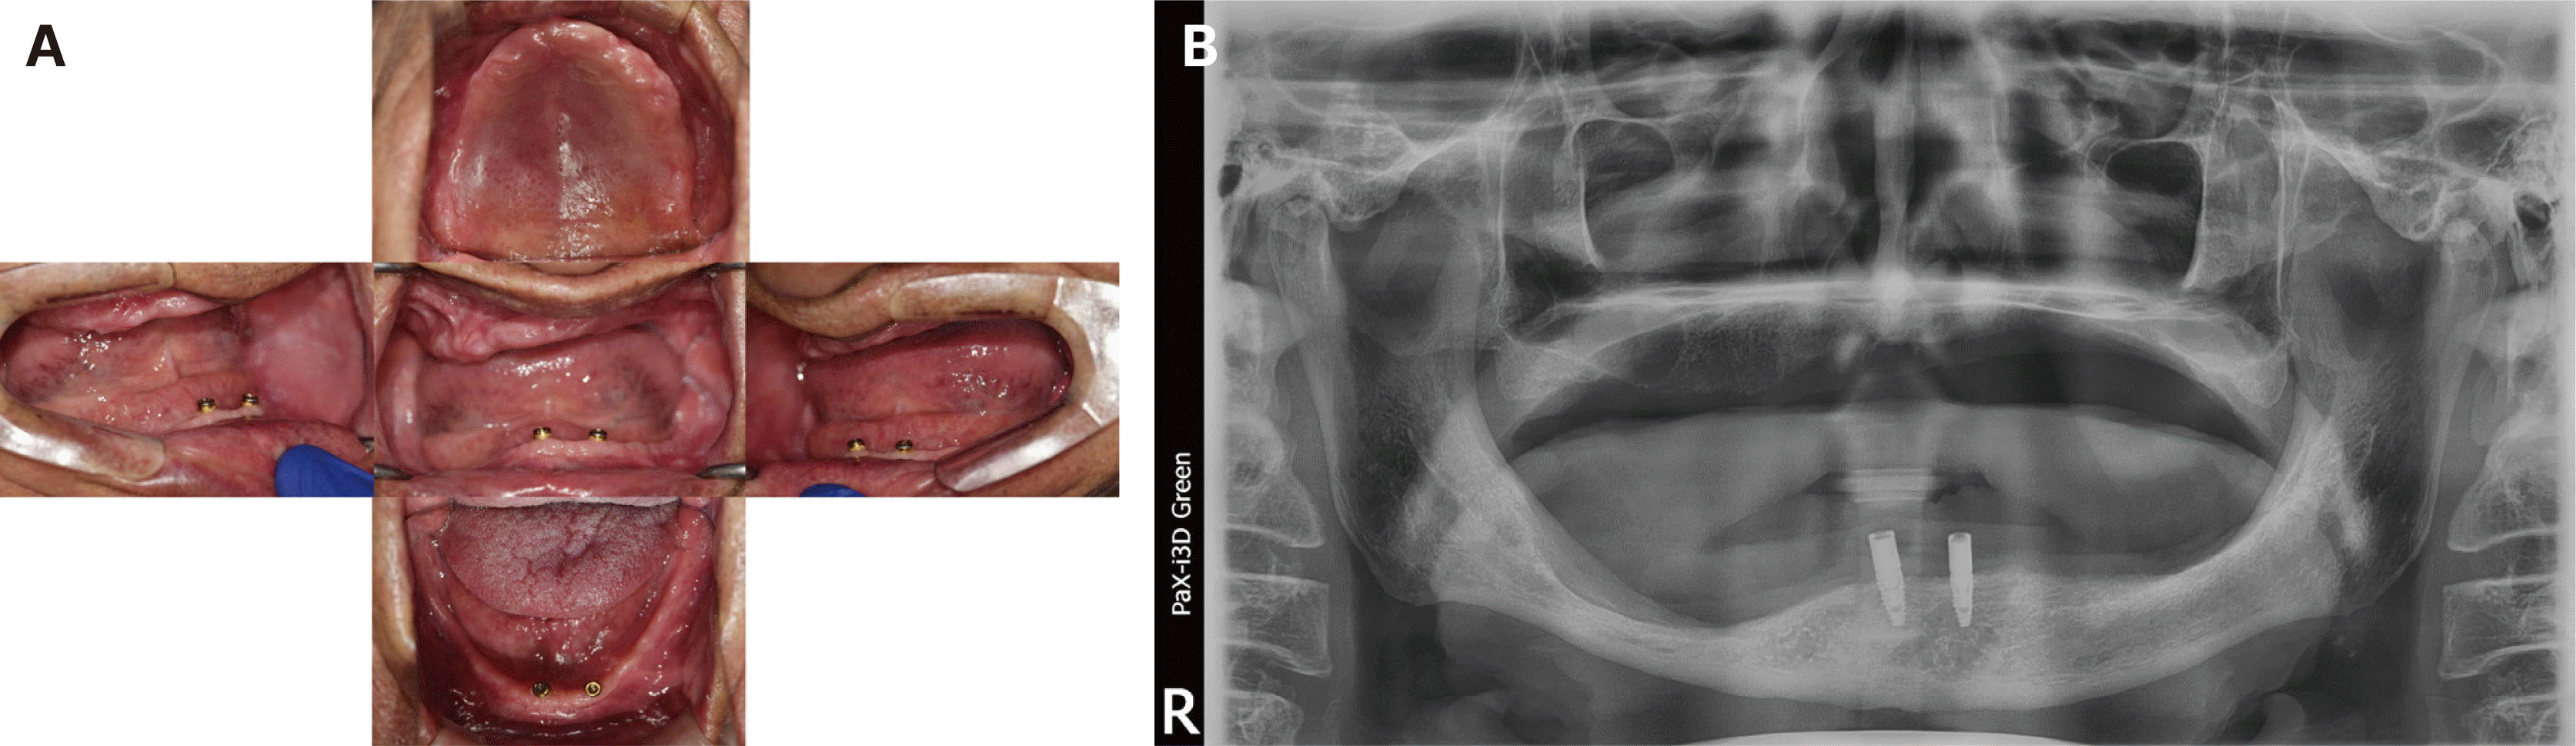

Fig. 8

Examination of patient 2 on the first visit. (A) Intraoral photos of the edentulous arch, (B) Panoramic radiograph of patient 2.

A 68-year-old male patient reported poor fitting of the old maxillary complete dentures and implant-supported mandibular overdenture, along with a loss of masticatory efficiency. This patient exhibited asymmetrical alveolar bone resorption on the left lower and right upper alveolar arches (Fig. 8). The old mandibular implant-supported denture was fabricated seven years ago and exhibited yellowish discoloration of the artificial teeth, and the maxillary complete denture was replaced two years ago due to a fracture. The old prostheses presented some acceptable clinical aspects, along with potential modifications. The two mandibular implants remained intact, contributing to the retention and stability of the current denture. The temporomandibular complex was in equilibrium with the current occlusal vertical dimension. The old dentures maintained a good fit to the alveolar ridges during the centric occlusion; however, the upper denture showed a visible decrease in stability during the lateral movement. The occlusal plane of the old dentures was horizontally deviated to the left to align with the uneven anatomical features of alveolar ridge (Fig. 9). A lack of posterior molar contact points and force distribution was noted using the conventional articulating paper and Shimstock film. Additionally, digital analysis suggested insufficient contact area on the left posterior side, with premature contacts detected on the right side during centric occlusion, as recorded by T-Scan Novus (Fig. 10).